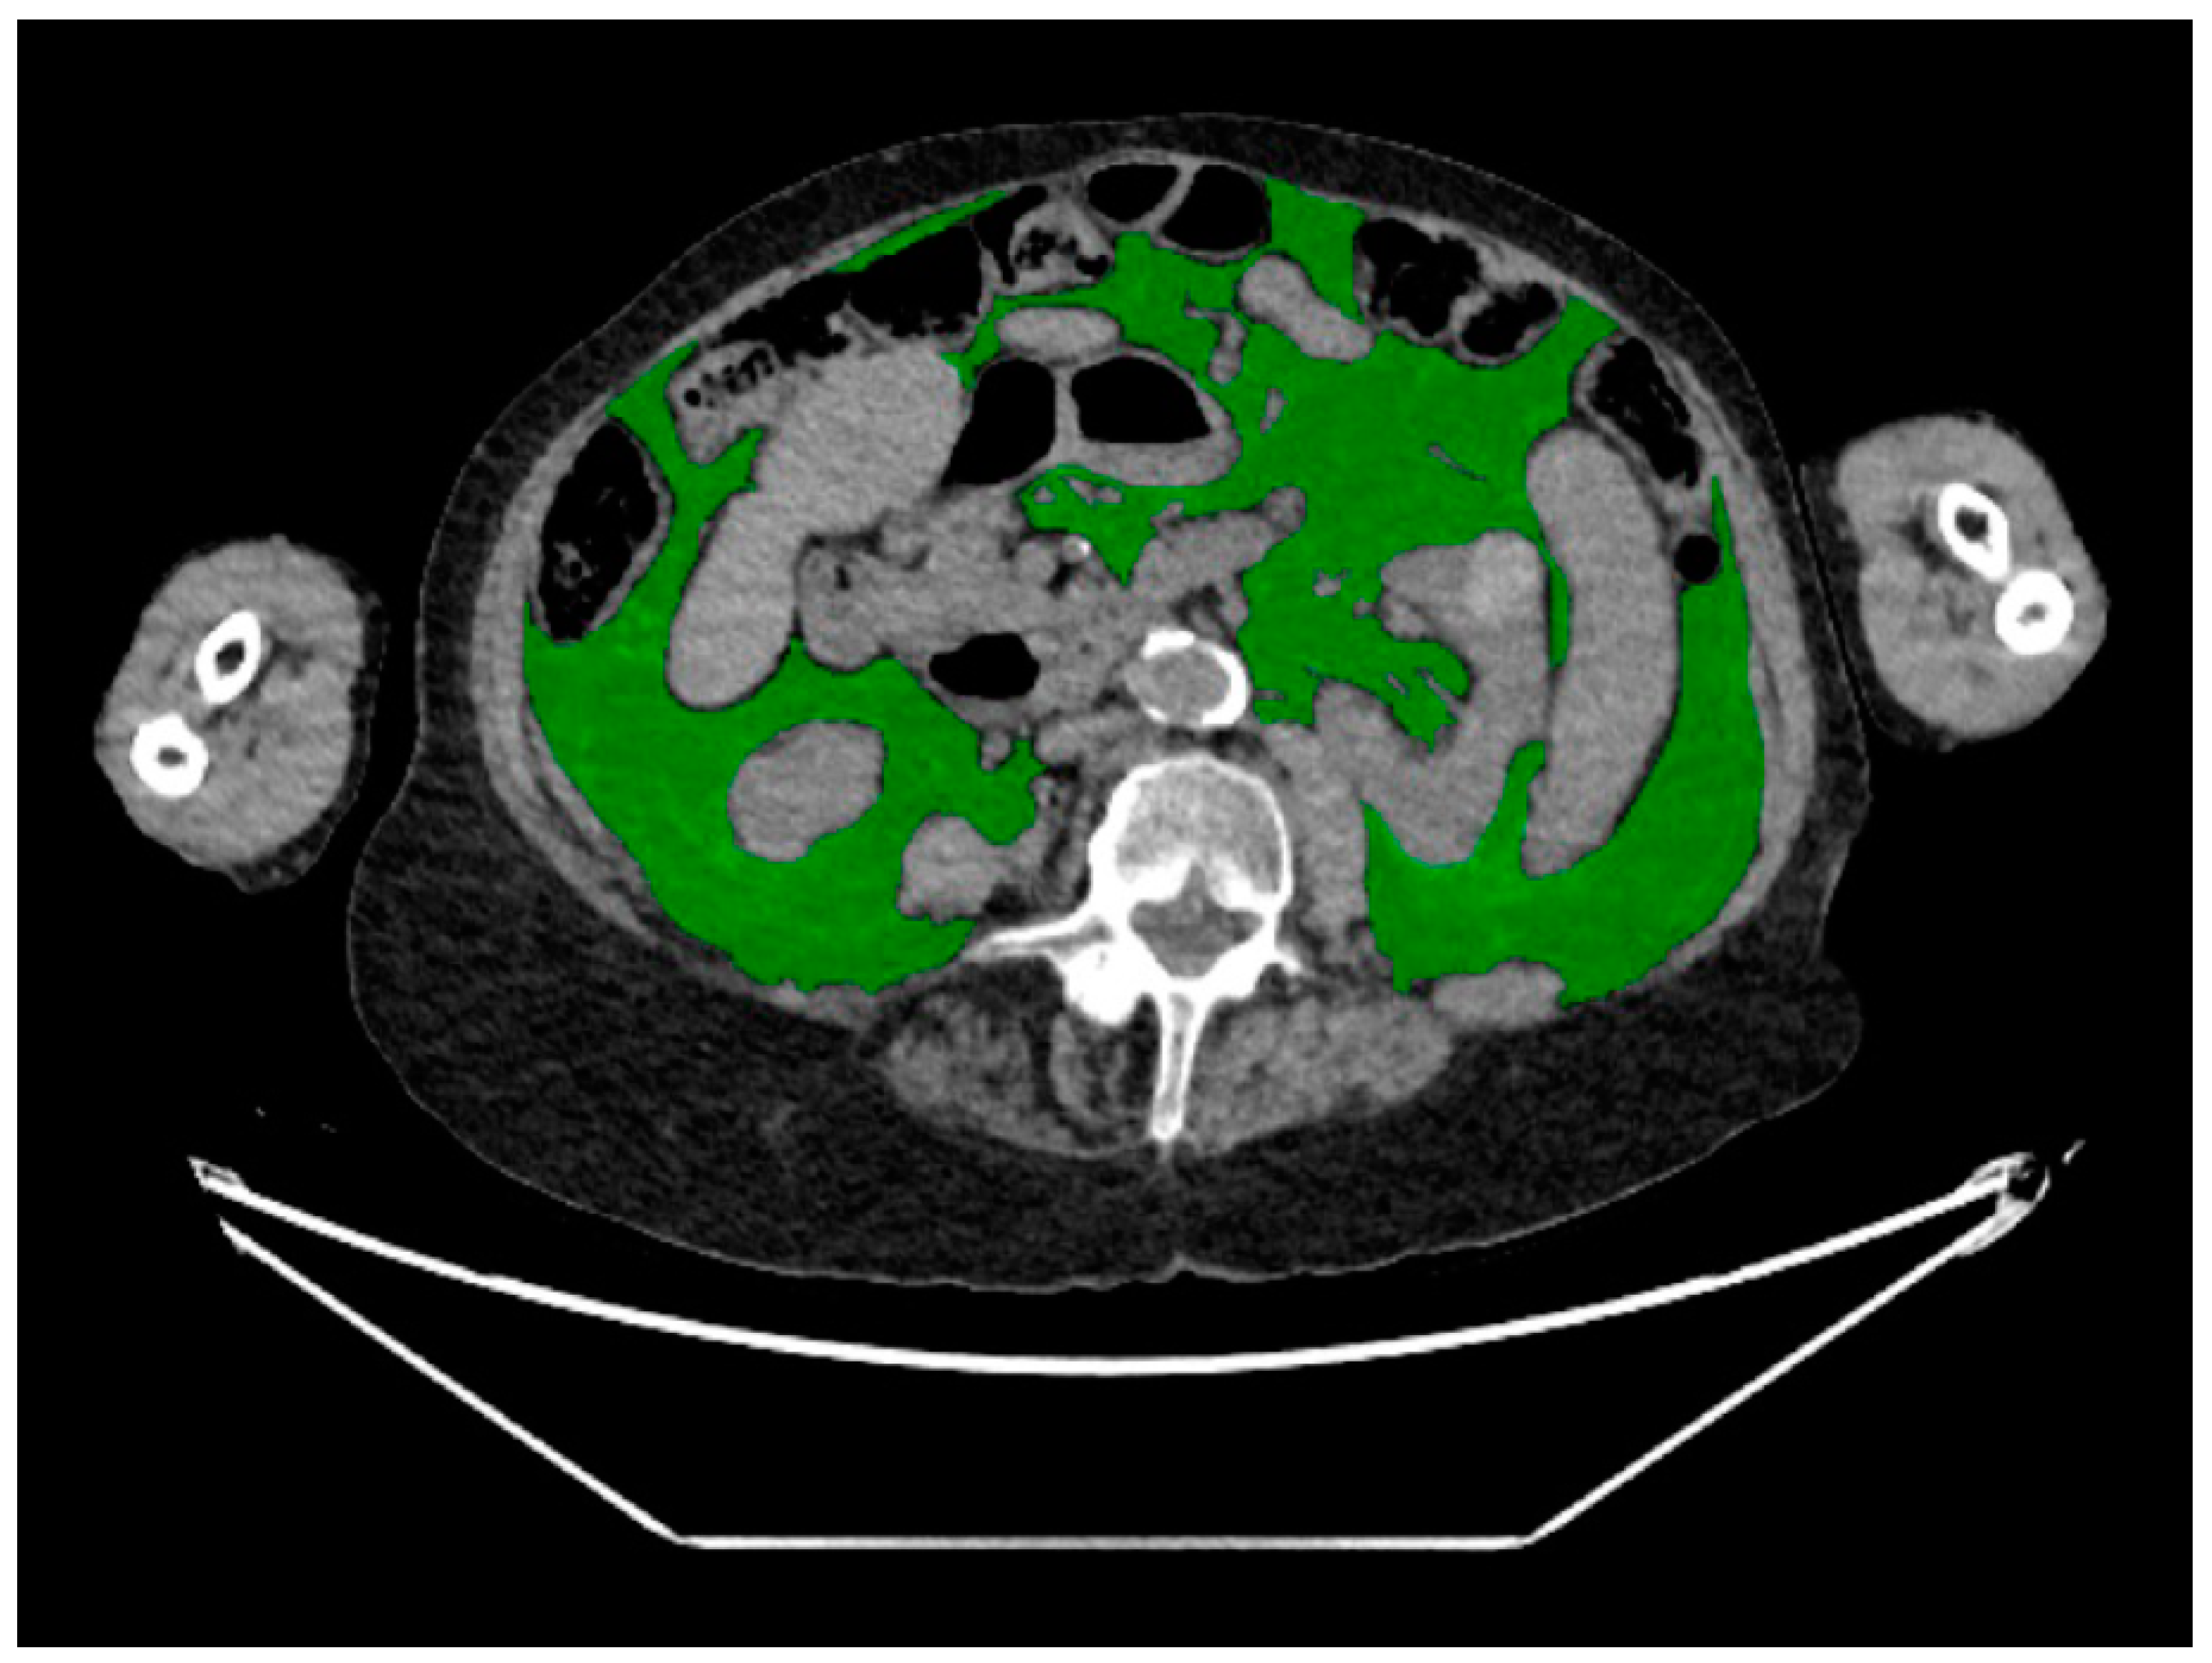

2.3. CT Body Composition Assessment

| Body composition measures a | Median (IQR) or % (n) |

| Visceral adipose tissue | |

| Area (cm2) | 124 (75–211) |

| Muscle | |

| Area (cm2) | 140 (116–165) |